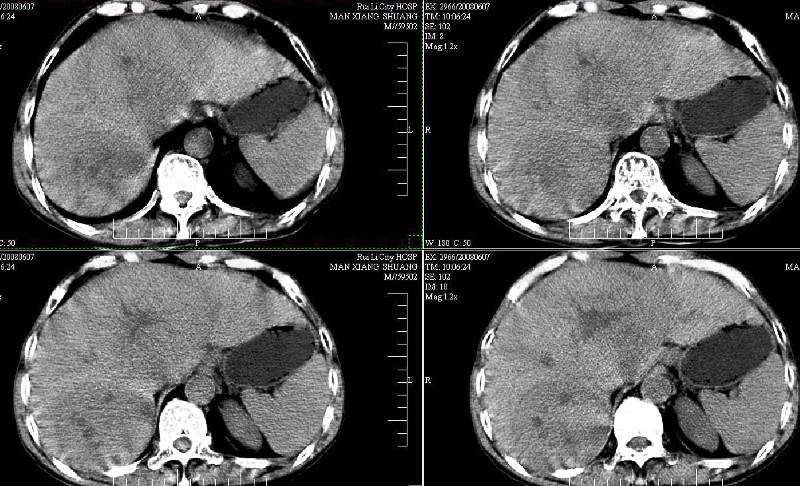

ct:肝癌腰椎转移。临床医生:肝脏、骨转移,肿瘤来自?前列腺?!

支持肝癌伴椎体转移瘤。腹膜后建议ct增强,好象有增大的淋巴结。

1、支持肝癌肝内及腰椎转移。

2、肝脏内好象有多个病灶,建议增强检查。